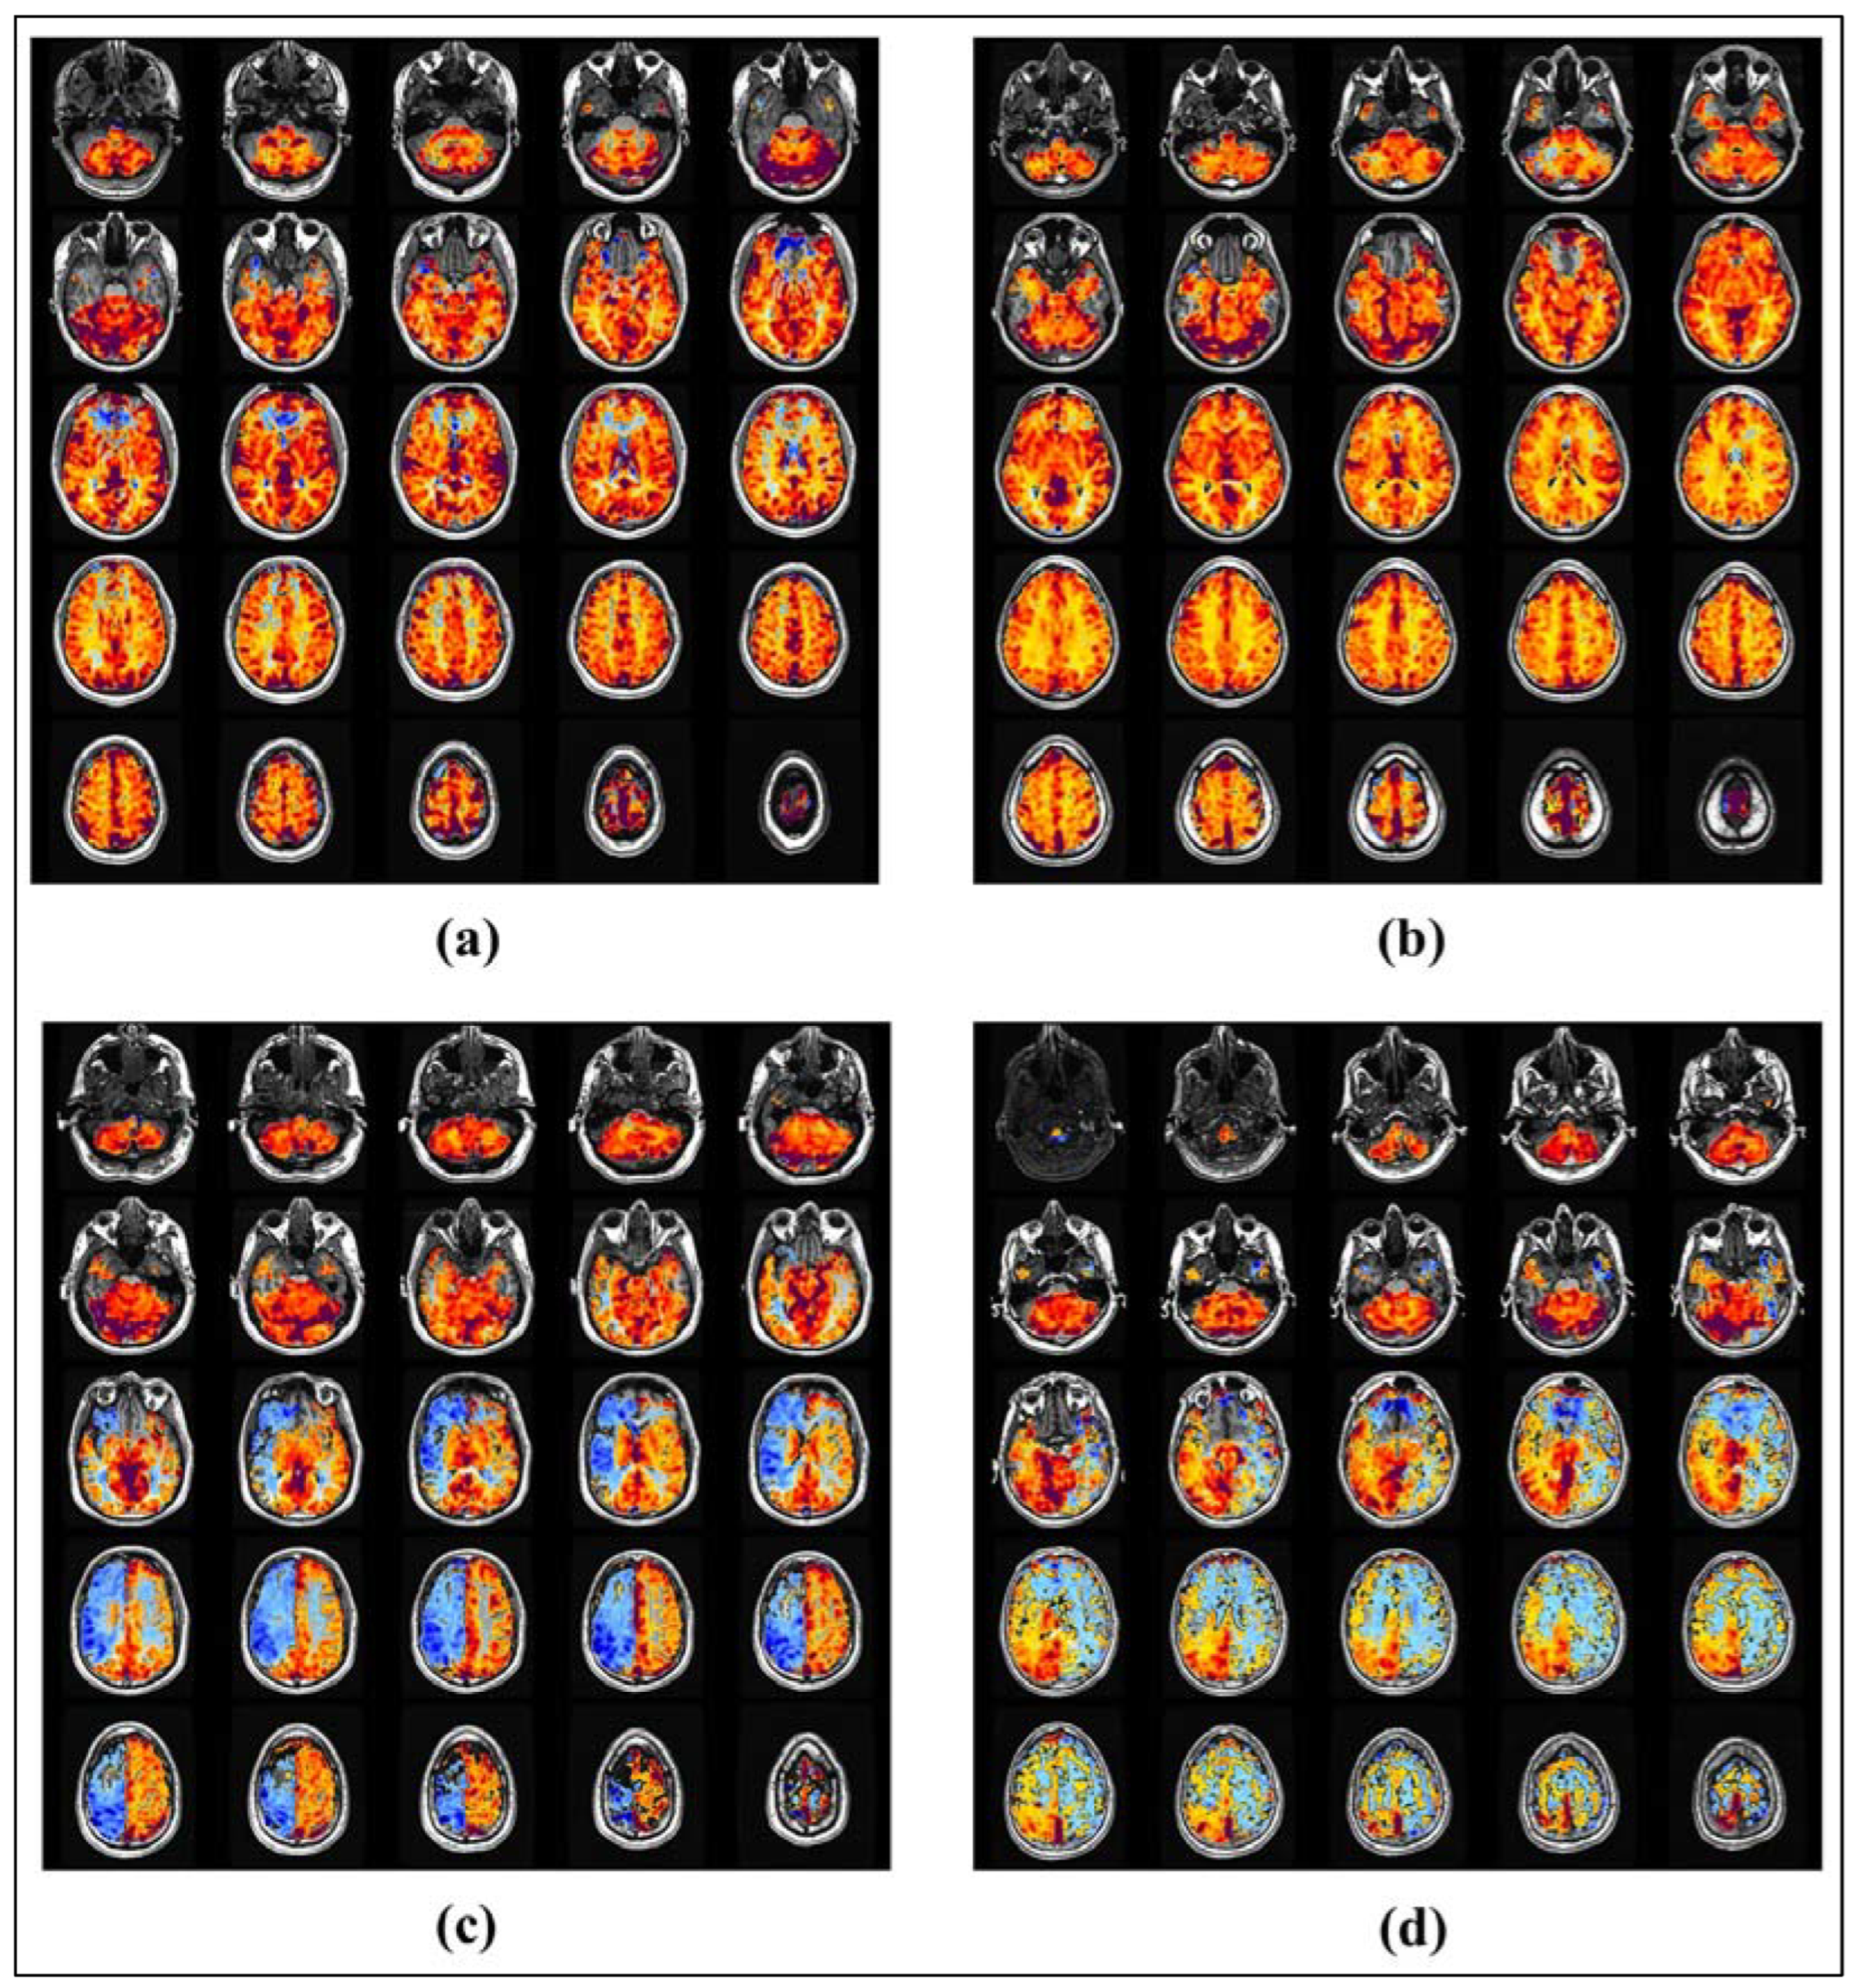

1.1. CVR: Clinical Workflow

3.1. Data Analysis and Pre-Processing